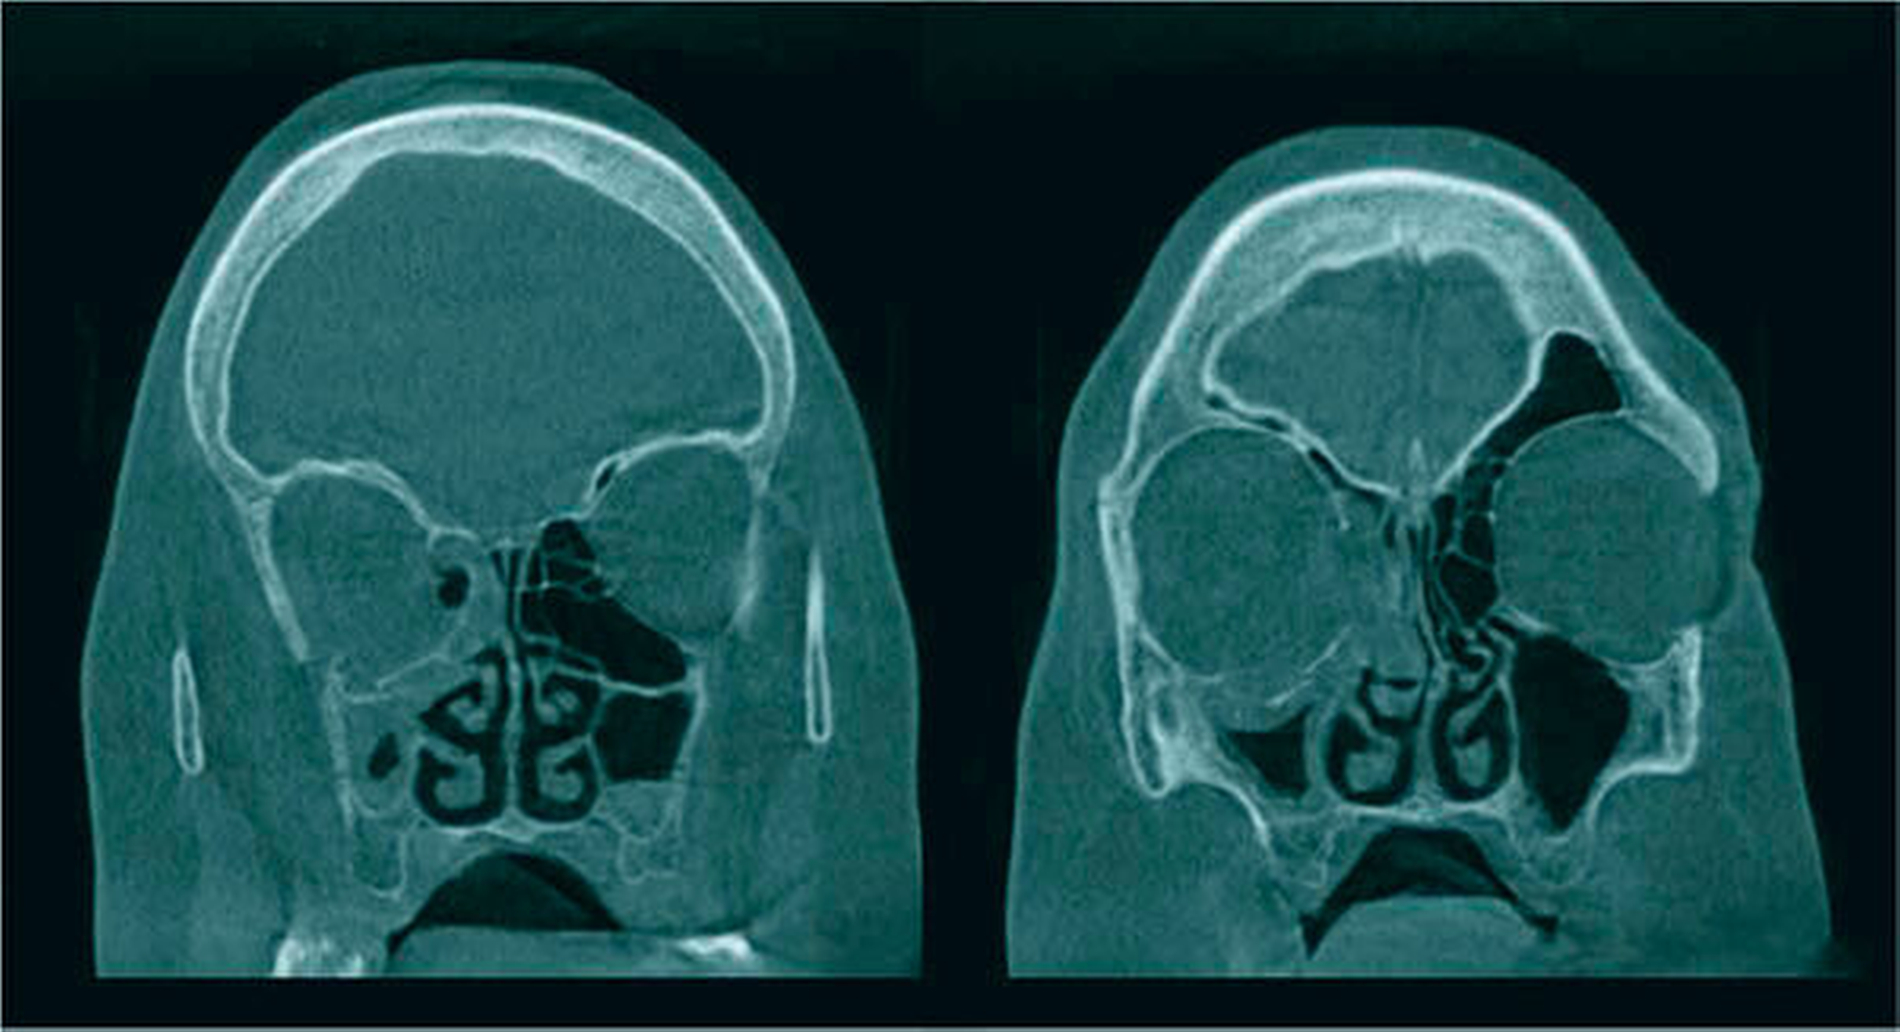

Die nach obligater klinischer Untersuchung zum Ausschluss eines intrakraniellen Blutungsgeschehens erfolgte Schichtbildgebung mittels Computertomografie (CT) bestätigt die Verdachtsdiagnose einer Orbitabodenfraktur rechts. Neben der auffälligen Dislokation des Orbitabodens mit geringgradiger Herniation von Fettgewebe nach kaudal in den angrenzenden Sinus maxillaris zeigt die CT zusätzlich eine Fraktur der Lamina papyracea, der fragilen lateralen Fläche des Siebbeinlabyrinths, mit ausgeprägter Fragmentdislokation nach medial (Abbildung 2). Ein retrobulbäres Hämatom liegt nicht vor, ebenso wenig bestehen Inkarzerationen ipsilateraler Augenmuskeln oder Anzeichen für ein intrakranielles Blutungsgeschehen. Weitere Frakturen lassen sich nicht nachweisen und klinisch imponieren keine Anzeichen für ein Schädel-Hirn-Trauma. Eine eingehende augenärztliche Untersuchung erbringt ferner keinen Nachweis einer traumabedingten Visusverschlechterung oder einer pathologisch eingeschränkten Bulbusmotilität.

Aufgrund der Komplexität der vorliegenden Fraktur, insbesondere unter Involvierung medialer Orbitaanteile mit ausgeprägter Dislokation der getrümmerten Fragmente, wird die Indikation zur operativen Intervention und Rekonstruktion des knöchernen Orbitarings mittels eines patientenindividuellen Implantats (PSI) gestellt. Zur Planung des Eingriffs, der intravenös-antibiotischen Therapie und der Überwachung wird die Patientin noch am Unfalltag stationär aufgenommen.